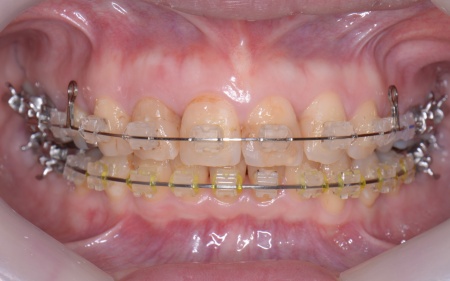

患者様の場合、骨格的な上顎前突が噛み合わせを乱している主な原因であることから、矯正治療では前歯を後方へ大きく動かすためのスペースを確保する必要があります。 そのため、今回は以下2つの方法を提案しました。 ①抜歯後、アンカースクリューを用いたワイヤー矯正 メリット:骨格的な上顎前突に対応しやすく、前歯を大きく後方へ動かすことができる ②取り外し可能な装置を使用するマウスピース矯正 メリット:装置が透明で目立ちにくく、取り外しができる 以上のメリットとデメリットを丁寧にお伝えしたところ、患者様は①のアンカースクリューを用いたワイヤー矯正を選択されました。 まず、上顎の左右奥歯を抜き、前歯を後方に動かすためのスペースを確保します。 治療の結果、前歯が正しく噛み合うようになり、横顔のバランスも整いました。 矯正治療終了後は、歯が元の場所に戻らないよう上下前歯に保定装置(リテーナー)を装着し、治療を終了しています。 |